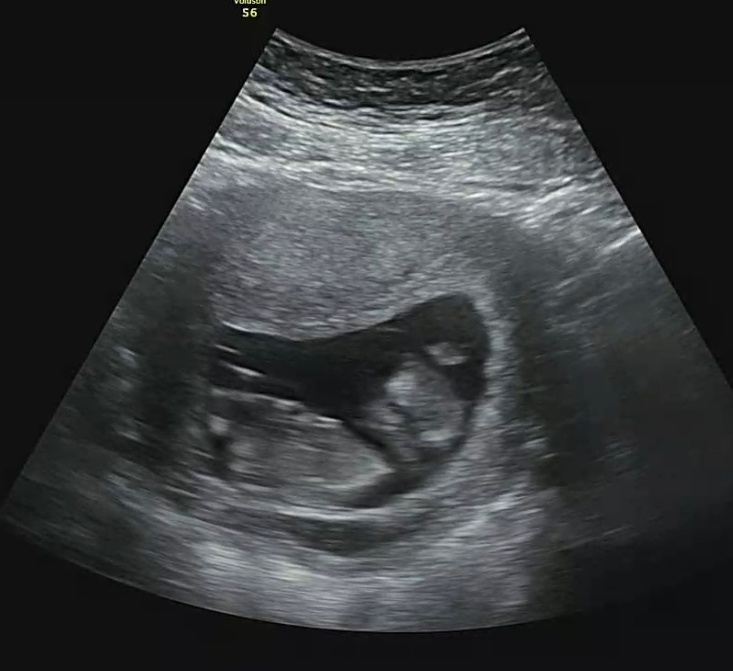

12주 3일 차부터 갑자기 생긴 피고임으로 질정을 넣고 있었다.

뚝딱이가 건강하니 양이 늘거나 흐르지 않으면 당분간은 안 와도 괜찮다는 말을 듣고 피 양도 줄어서 안심하고 있던 날

피고임이 3.5cm로 조금 커졌다.

왜 커지는지는 알 수 없지만 아기집도 크고 뚝딱이도 건강하니 큰 문제는 없을 거라는 선생님의 말씀..

양수검사는 16주 이후부터 가능하다고 들었는데 선생님께서 초음파를 보시곤 오늘도 할 수 있을 것 같다 말씀해 주셔서

당일에 검사를 하고 왔다.